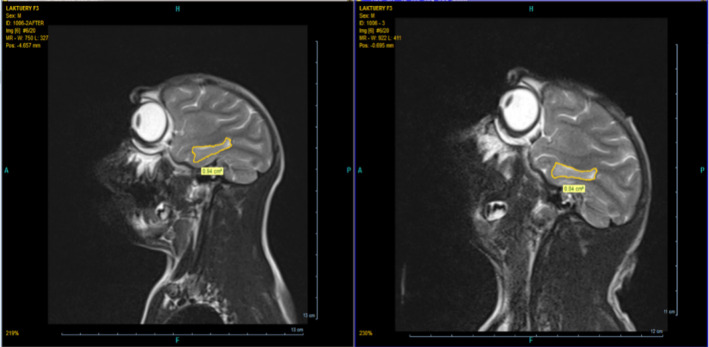

Methods: To achieve this goal, macaques were studied for their cognitive functions, expression of the NMDA receptor gene, MRI-assisted analysis of brain anatomy, and variations in blood sodium and potassium concentrations. The experimental group of macaques was exposed to a 3 kV/m HV field for 4 hours a day for 1 month. Computational models were then evaluated using experimental parameters.

Results: According to the results, exposure to HV electric fields reduced the expression of the NMDA receptor gene, as well as a decrease in the levels of sodium and potassium ions in the blood plasma. Additionally, MRI-assisted analysis showed reduced hippocampus and amygdala size after exposure to the electric field.